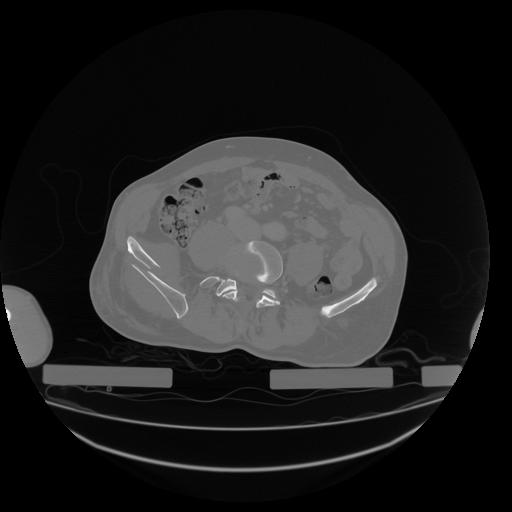

34 CUERPO,CE,Vol,1.0,CUERPO,,